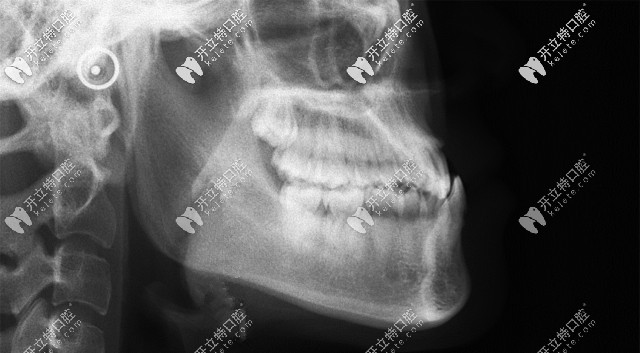

從這張頭顱側(cè)位片,可以清晰的看到顧客牙齒情況是骨性反頜(地包天)▲